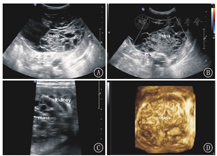

MCDK是婴幼儿肾脏最常见的囊性发育异常性疾病,发病率约为1/3 000[3],是一种非遗传性完全性肾脏发育不良,由于其多囊的超声表现常误诊为多囊肾。因为双侧MCDK患儿不能存活,所以单侧发病多见,患侧肾脏多无功能,同侧输尿管多闭锁或未发育,对侧肾多发育正常,由于对侧健康肾脏代偿性增大,肾功能正常。单侧MCDK患者,临床多无特异性症状和体征,预后良好,一般也不发生癌变,可手术切除[4,5];如果对侧肾脏发育异常,如常合并肾盂输尿管连接部梗阻、重复肾、膀胱输尿管反流等[6],预后则取决对侧肾脏的异常严重程度,如同时伴肾外畸形,则预后不良。MCDK典型的超声影像学特点是患侧肾脏失去正常形态,由数量不等、大小不一的多个薄壁囊肿组成,各囊肿互不相通,囊肿间由于结缔组织增生看不到肾实质或仅有少部分肾实质(图1)。同侧输尿管多不显示。同时要仔细观察对侧肾脏是否发育正常,有助于评估预后。大多数患儿在产前超声检查时发现,出生后的患儿需要超声密切随访观察肾脏发育状况[7],该病可随时间推移而发生退化,最终演变为小瘤样组织。当患儿出现血压增高或患侧肾脏合并巨大囊肿时需手术切除,因此,对MCDK囊肿大小的评估至关重要。本病与重度肾积水不同,一般情况下,重度肾积水内的多个液性囊腔是由明显扩张的肾盂肾盏形成的,彼此连通,囊腔间可见菲薄的肾实质,探查肾盂输尿管连接部具有重要的诊断意义[8]。

ARPKD是一种儿童最常见的遗传性囊性肾脏疾病[9]。该病存在第6号染色体上的PKDH1基因突变[10],子代个体中1/4发病,而父母双方均无本病表现。肾脏的主要病理学改变为集合管及远端肾小管弥散性扩张,呈放射状排列,从髓质扩展到皮质,部分患者扩张的囊腔内有钙盐沉积或尿酸盐小结晶可见。患儿均出现不同程度的先天性肝脏纤维化。根据发病年龄、肾小管受累数量及肝脏损害程度分为4型:围生期型、新生儿型、婴儿型和少年型。前两型在胎儿或新生儿期就表现为双侧肾脏对称性增大且回声异常,预后较差,通过超声检查可确诊。后两型出生时肝肾病变较轻,无明显临床症状和体征,随着年龄的增长,患儿逐渐出现消化或泌尿系统症状而确诊[11,12]。以往认为肾脏病变程度与肝脏病变程度成反比,年龄越小,肾脏病变越重的患者,肝脏纤维化的程度反而越轻,而有研究认为二者的发展各自独立,并无相关性[13,14]。年龄越小的ARPKD患者肾脏超声影像学特点越典型。胎儿或新生儿患者往往出现双肾对称性明显增大,但并不失去椭圆形的外形,皮髓质分界不清,有时可见外围一圈薄薄的正常肾皮质,严重者肾被膜显示不清晰;低频凸阵探头显示髓质回声增高的典型超声改变,是由于髓质内数量众多的微小囊肿及扩张的小管所产生的声波多重反射形成;线阵高频探头可显示髓质内弥散密集分布的条状或管状微小囊腔结构(扩张的集合管和远端肾小管)或皮髓质散在多发小囊肿,部分患儿囊腔内有钙盐沉积或尿酸盐小结晶形成的成簇成团的点状强回声,为本病的特异性超声表现(图2)。而年龄较大的ARPKD患儿,病变主要以肝胆改变为主、肾脏病变不明显[15],双肾呈轻、中度增大,可能是由于患儿年龄偏大,部分患肾在病程进展中逐渐缩小,因此肾脏增大的患儿较少[9]。有学者使用超声追踪随访ARPKD患者,发现肾脏体积随年龄增大可保持不变,也可逐渐缩小[16]。也有学者认为ARPKD患肾体积的改变与肾功能并无确切相关性[17]。因此,对较大年龄患儿诊断ARPKD,肾脏大小不是诊断的关键,髓质内有无微小囊腔结构及肾实质内有无散在囊肿才是本病主要的诊断依据。怀疑ARPKD的患儿,尤其是对于较大年龄患儿,常规探查肝脏有助于ARPKD的诊断。观察肝内胆管有无扩张,肝叶比例有无改变,肝脏有无纤维化及纤维化的程度等(图2)。一般情况下,肝叶比例改变均表现为左叶增大、右叶缩小[18]。结合临床特点、基因检测结果和超声影像学特点,不难做出ARPKD的诊断。